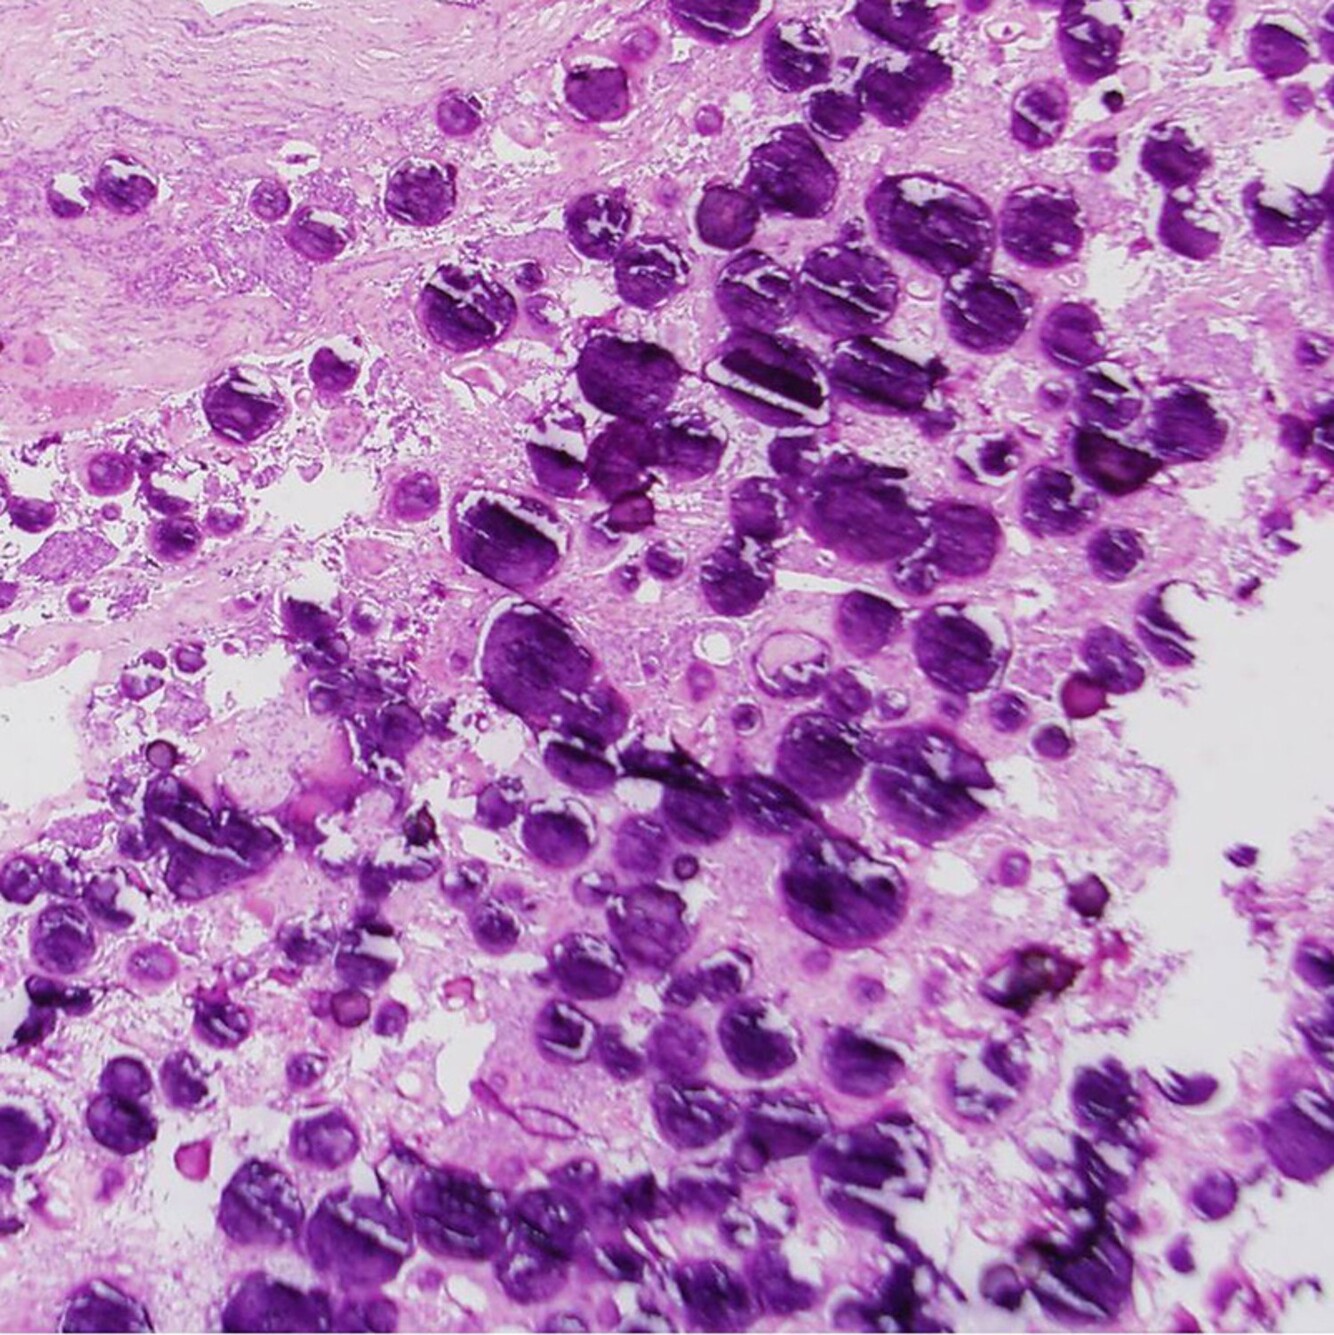

You are evaluating a 65-year-old woman with the onset of low-grade headache and occasional word finding difficulties. Imaging demonstrates a left-sided ring-enhancing mass. You complete a gross total resection and the final pathology is demonstrated below. What gene amplification is often seen in this tumor type?

The pathology slide demonstrates evidence of glioblastoma, notable for pseudopalisading necrosis. GBM often demonstrates amplification of EGFR, and this can also be a reason for tumor transition from anaplastic astrocytoma to GBM.